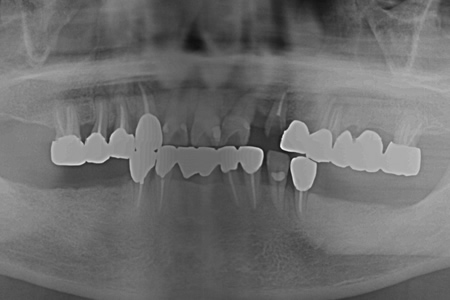

レントゲン室にご案内して、口腔内のレントゲン撮影を行います。

必要に応じてパノラマレントゲン撮影も行います。